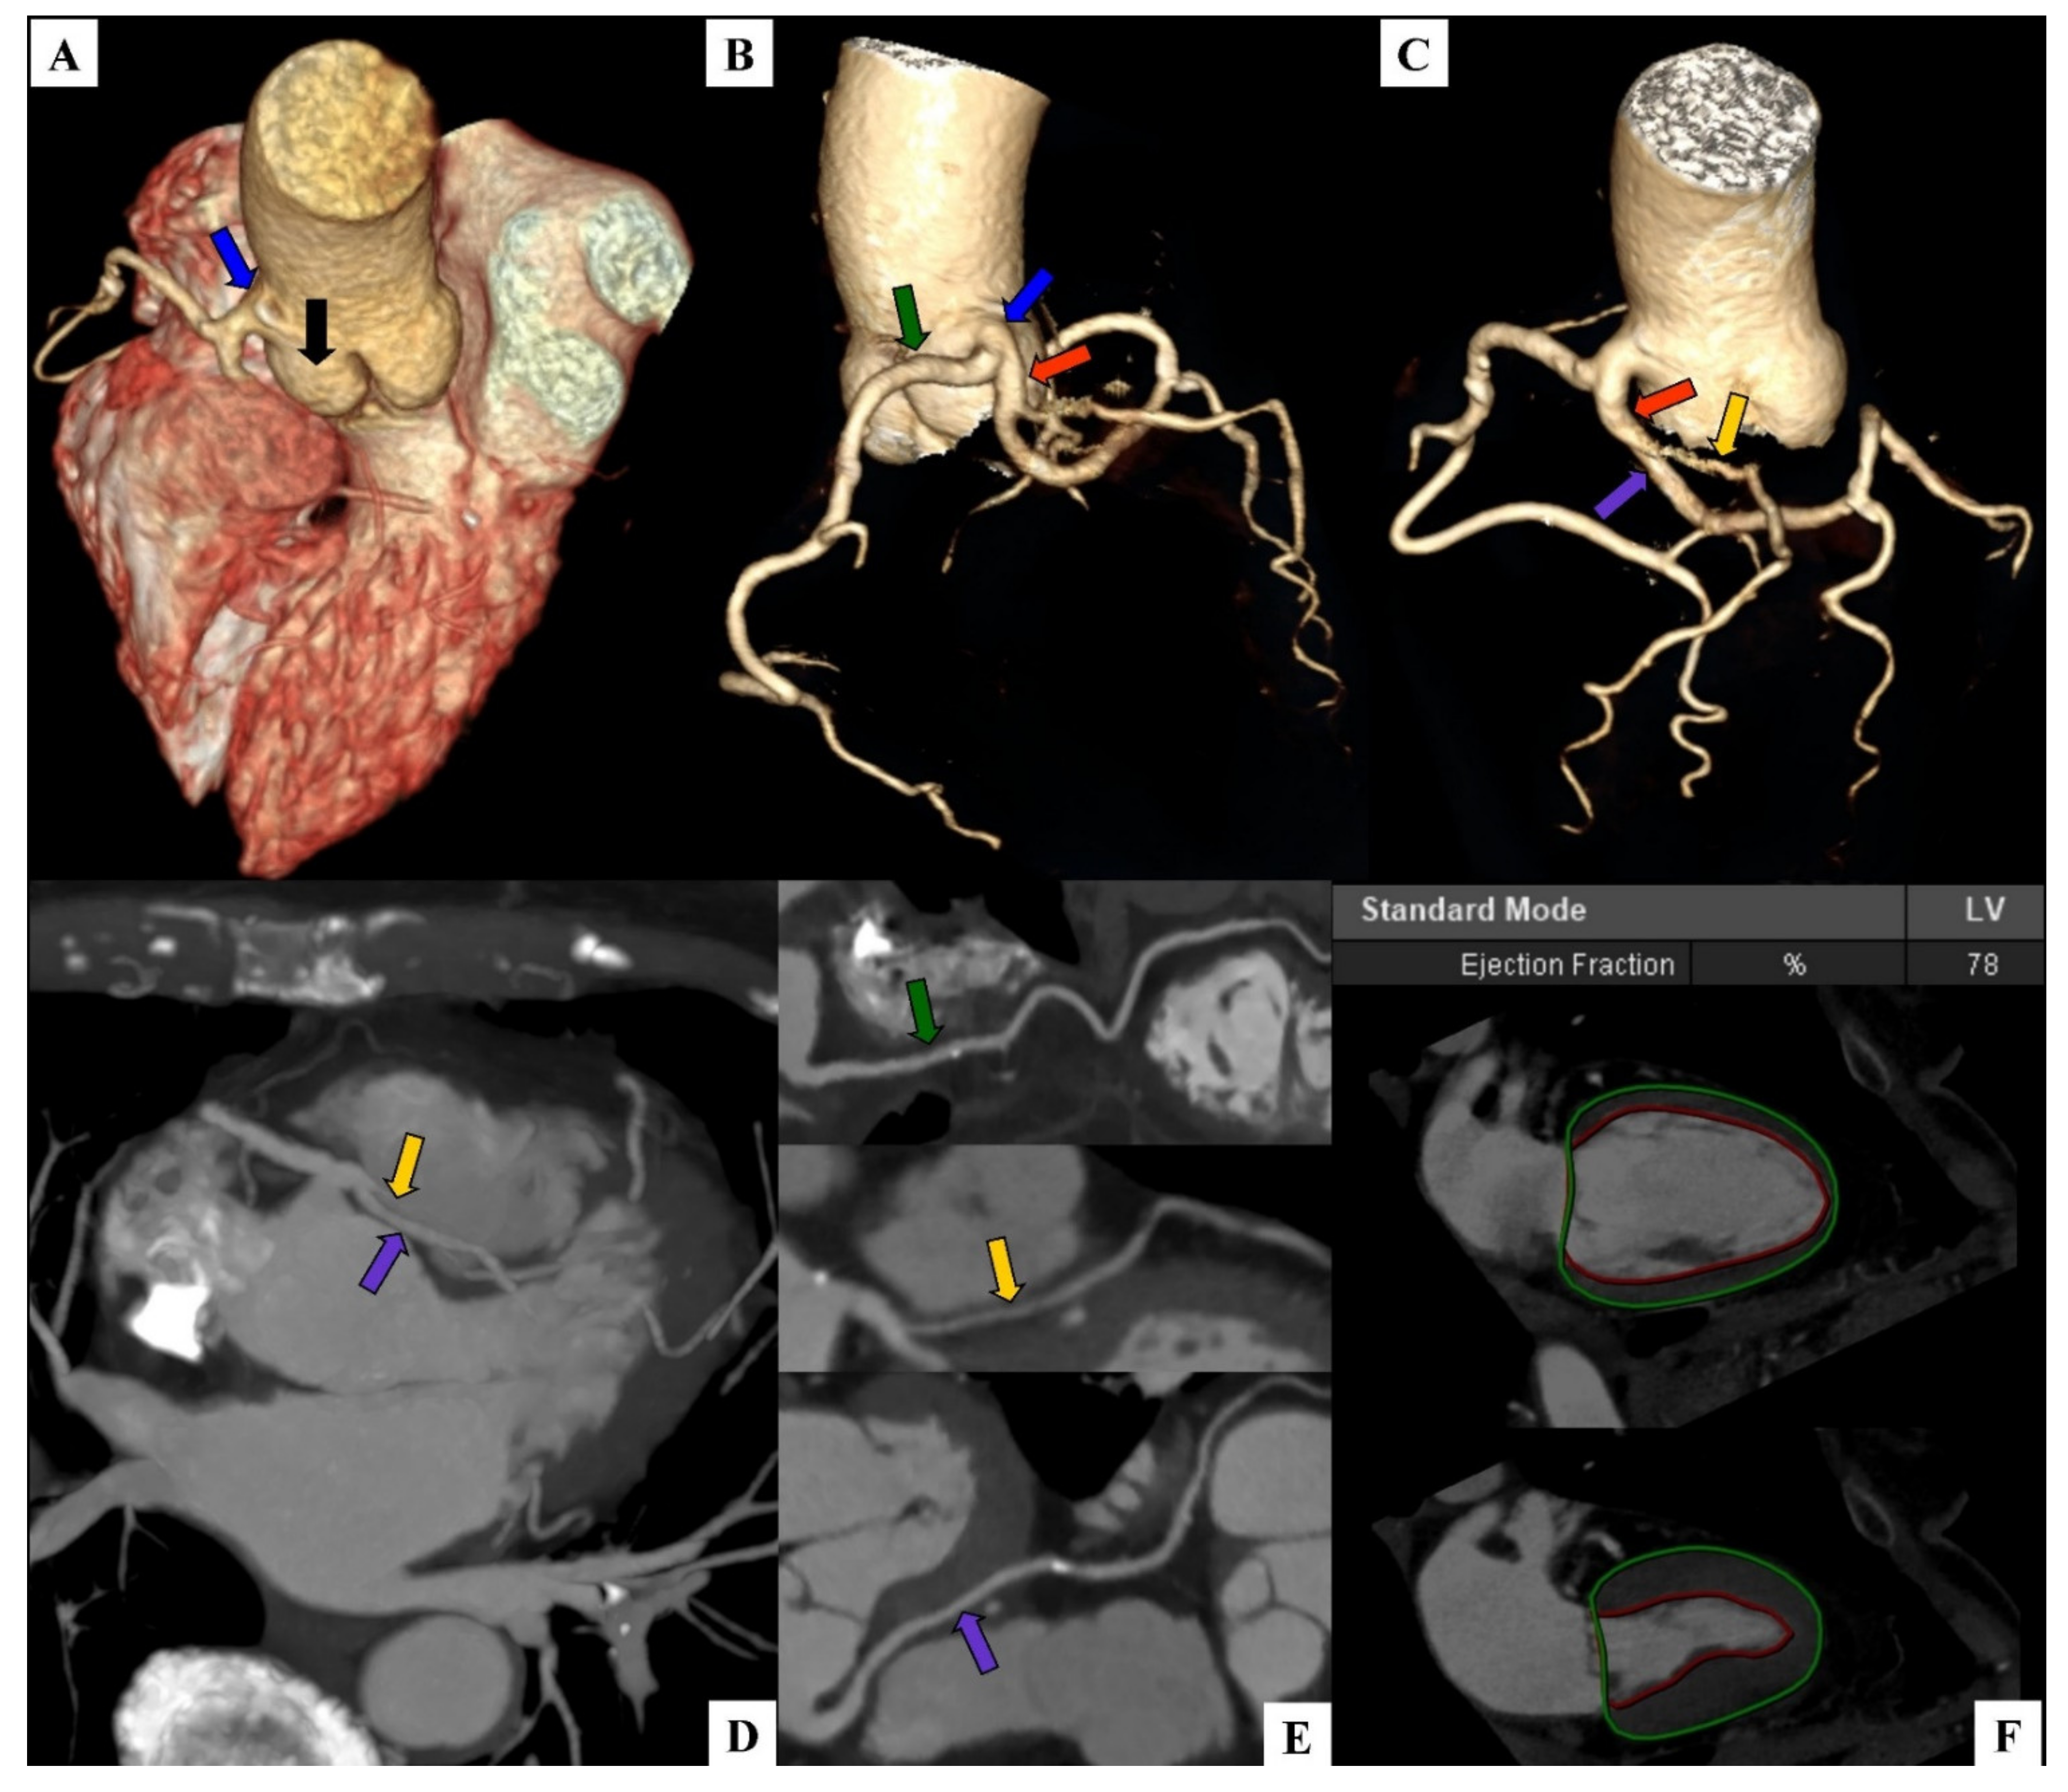

A Single Coronary Artery Originating from the Right Coronary Sinus with a Typical Course of the Right Coronary Artery and the Interarterial Course of the Left Main, Left Anterior Descending, and Left Circumflex as an Example of a Rare Case of High-Risk Coronary Anomaly

2. Case Report